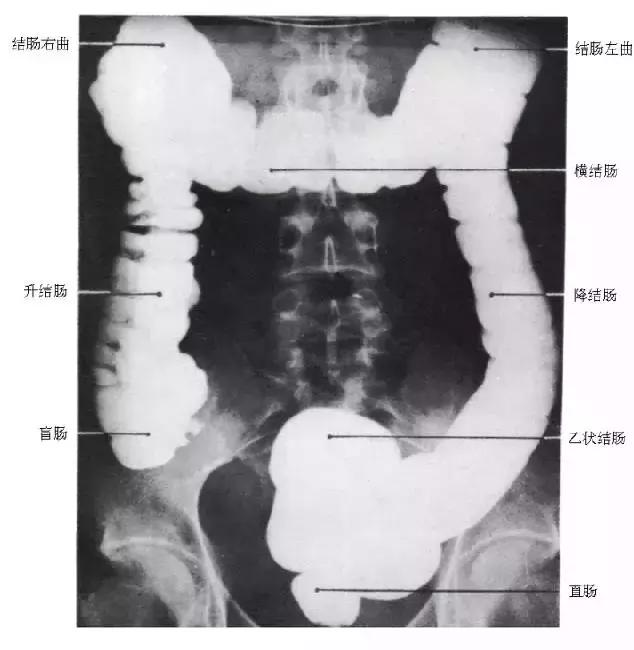

十、结肠

图19 结肠造影

图20 1 结肠脾曲,2 结肠肝曲,3 升结肠,4 横结肠,5 降结肠,6 结肠袋,7 回盲瓣,8 盲肠,9 乙状结肠,10 阑尾,11 直肠